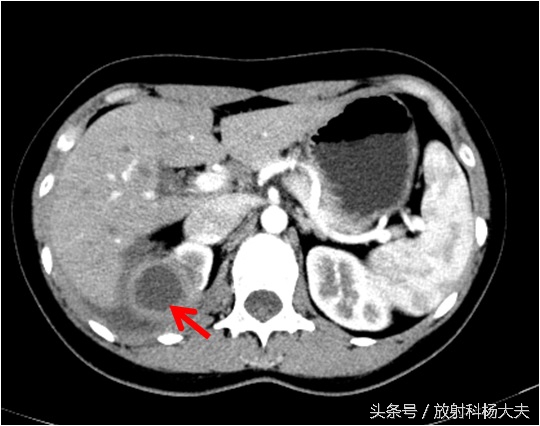

骨科接着开了腰椎CT,骨科大夫怀疑背部是一个窦道,猜测窦道可能是脊柱旁,因此开了腰椎CT平扫,腰椎CT扫描的时候是以腰椎和椎间盘为主的,范围不大,但我们却在不大的范围内发现了问题,除了窦道,肾上有东西!但腰椎CT平扫实在难以评价,因此做了腹部增强CT,发现了实属罕见的情况:那个确实是个窦道,如下图红箭所示,窦道外口在体表,也就是流水的地方。窦道的上口却是在肾脏!

如下图,右肾上长了个东西,囊性的,壁挺厚。